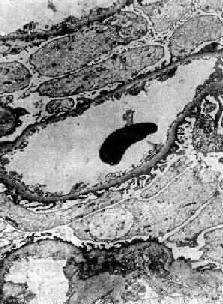

光学显微镜下,肾小球无明显变化或仅有轻度节段性系膜增生。电镜下见弥漫性肾小球脏层上皮细胞足突消失(图12-20),细胞内高尔基器和内质网增多,并可见脂滴。细胞表面常有多数微绒毛形成。足突消失不仅见于脂性肾病,也常见于其他原因引起的大量蛋白尿和肾病综合征。经过治疗或蛋白尿等症状缓解后,脏层上皮细胞的变化可恢复正常。

图12-20 轻微病变性肾小球肾炎

电镜下见肾小球毛细血管上皮细胞部分足突消失